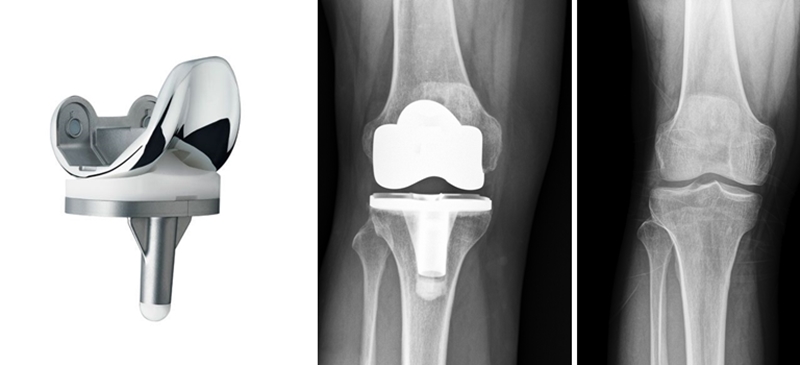

การผ่าตัดเปลี่ยนข้อเข่าเทียมบางส่วน หรือเรียกสั้นๆ ได้ว่า UKA คือ การผ่าตัดเอาผิวข้อเข่าเฉพาะส่วนที่เสียหายหรือเสื่อมสภาพออก นั่นคือด้านในหรือด้านนอก (Medial or Lateral Compartment) เพียงด้านเดียว ผิวข้อเข่าที่เสื่อมจะถูกแทนที่ด้วยโลหะอัลลอยด์ โดยมีแผ่นโพลีเอทิลีนซึ่งทำหน้าที่เป็นตัวรองรับแทนที่หมอนรองกระดูกเดิมกั้นระหว่างโลหะ

(Figure 5-8) วิธีนี้ถือเป็นนวัตกรรมพิเศษที่คิดค้นขึ้นเพื่อรักษาพยาธิสภาพที่เข่าเฉพาะกลุ่มผู้ป่วยให้ตรงจุดมากที่สุด และเป็นเทคโนโลยีการผ่าตัดแผลเล็ก ที่ช่วยเก็บผิวข้อเข่ารวมถึงเอ็นและเนื้อเยื่อเดิมที่ยังมีสภาพดีไว้ ทำให้เกิดความรู้สึก เสมือนธรรมชาติ หลังการผ่าตัด ซึ่งเป็นจุดเด่นสำคัญของการผ่าตัดด้วยวิธีนี้

(Figure 5-8: Unicompartmental Knee Arthroplasty: UKA)

โดยทั่วไปแล้วข้อเข่าเสื่อมที่เกิดจากการใช้งานตามวัย มากกว่า 90 % มักจะเริ่มมีการเสื่อมที่ผิวข้อเข่าด้านในเพียงด้านเดียว ทำให้เหมาะต่อการรักษาโดยการผ่าตัดเปลี่ยนข้อเข่าบางส่วน ซึ่งเป็นวิธีที่สามารถเก็บรักษาผิวข้อเข่าหรือกระดูกอ่อน ตลอดจนเส้นเอ็นต่างๆ ภายในข้อเข่าที่ยังมีสภาพดีไว้ แทนที่จะทำการผ่าตัดเปลี่ยนข้อเข่าทั้งหมด และยังให้ความรู้สึกเสมือนธรรมชาติของข้อเข่าได้อีกด้วย